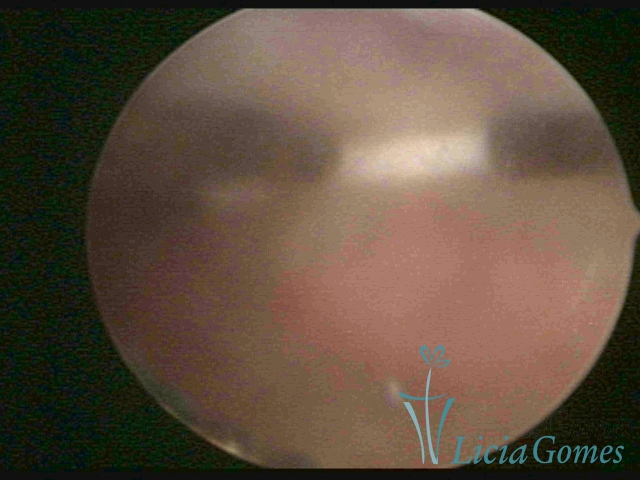

Uterine cavity with IUD and accumulated light mucus